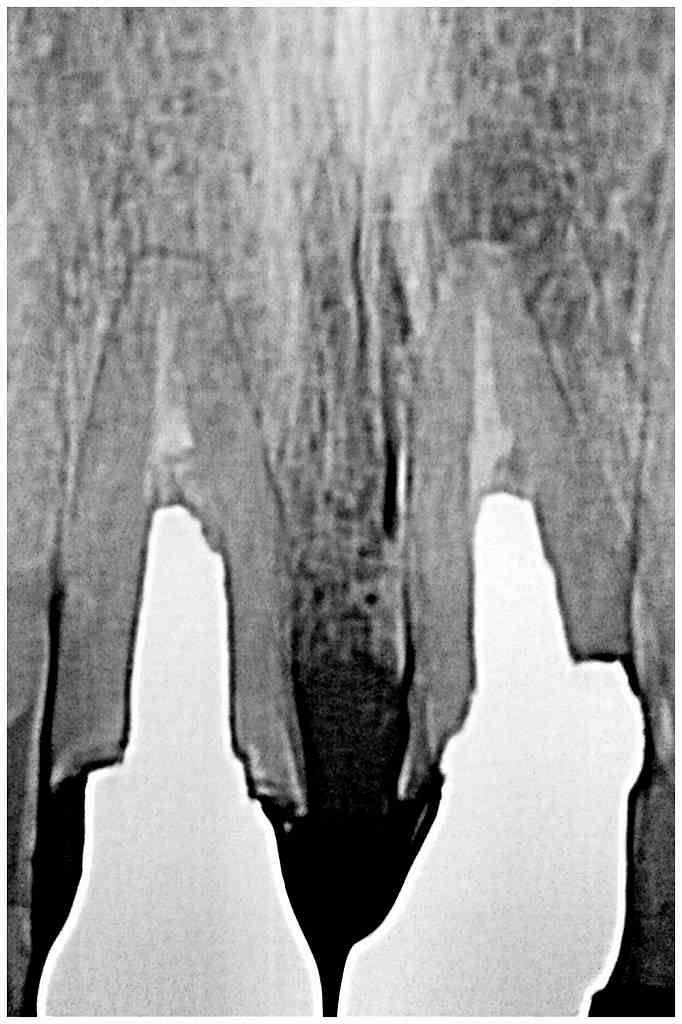

デンタルレントゲンになります

歯が割れてきていました